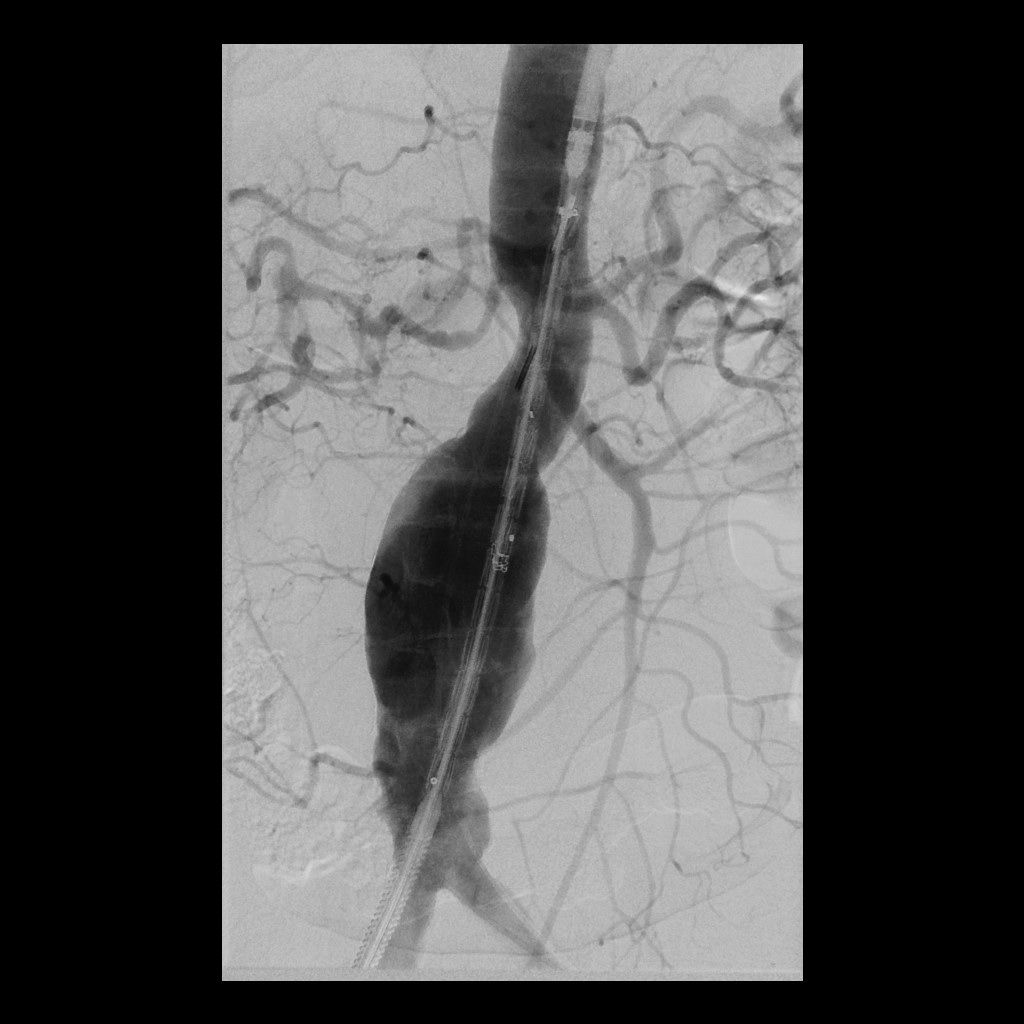

Eine Erweiterung der Bauchschlagader kann das Risiko eines Gefäßeinrisses stark erhöhen (Aneurysma). Die Radiologie bietet hier zusammen mit den Kollegen der Gefäßchirurgie ein minimal-invasives Verfahren zur Ausschaltung des Aneurysmas an. Dies geschieht mittels Stent-Prothese (endovascular aortic repair; EVAR).